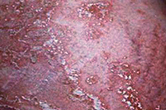

看图读懂不同类型的皮炎

专家提醒:皮炎最明显的症状就是瘙痒,但是引起皮炎的病因各有不同,不能一概而论,需要专业的皮肤专家综合诊断。

危害:红斑、水肿,可伴有丘疹、丘疤疹、水疱或糜烂、渗出。

危害:水疱、红肿及渗出减少,出现结痂及脱屑。

危害:皮肤粗糙,苔藓样变,可伴有色素沉着或色素减退。